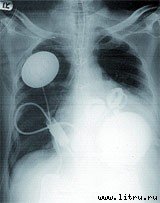

И все-таки, несмотря на радужные перспективы генеральной линии, они еще очень долго останутся лишь перспективами. Тем более сильное впечатление производят успехи «обычных» технологий изготовления органов из подручных, так сказать, материалов. Несомненный хит прошедшего года — искусственное сердце Abiocor. Собственно, впервые этот девайс был имплантирован человеку еще 21 августа 2001 года (а началом программы по его созданию была инициатива тогдашнего президента США Линдона Джонсона, объявленная в мае 1964 года [В годы правления Джонсона его имя связывали в основном с политикой эскалации войны во Вьетнаме, начавшейся с инцидента в Тонкинском заливе 2 августа того же 1964 года и унесшей сотни тысяч жизней. А в наши дни Джонсон — тот, в честь кого назван космический центр НАСА, да еще и инициатор создания искусственного сердца. Иронично получилось]; в Японии аналогичная работа велась с 1960 года). Abiocor пока что помог лишь немного продлить жизнь четырнадцати безнадежным пациентам (лучшие результаты были у двоих — они прожили после операции десять и семнадцать месяцев, и лишь один был выписан из больницы домой). Устройство работает от батарейки, которую надо подзаряжать (индукционно, через кожу) каждый час. Однако очевидно, что это полностью имплантируемое искусственное сердце — лишь первый шаг. Фирма ABIOMED сейчас тестирует искусственное сердце второго поколения, которое, как предполагается, должно работать в течение пяти лет (нынешняя модель рассчитана на восемнадцать месяцев). Но что же произошло в сентябре прошлого года, спустя пять лет после первой операции? Почему этот момент был сочтен специалистами ключевым и широко освещался в СМИ всего мира?

По очень простой причине — причем не медицинской и не научной, а чисто экономической. Abiocor разрешили продавать.

Формально это звучит так: искусственное сердце, созданное ABIOMED, получило «одобрение для гуманитарного использования в исключительных случаях» (humanitarian device exemption) от Администрации по лекарствам и пищевым продуктам США (Food and Drug Administration, FDA). Под «гуманитарным использованием» понимают отнюдь не «использование для людей», как решили некоторые наши популярные ресурсы. Речь идет о применении в очень ограниченном объеме — операций не должно быть более четырех тысяч в год. А «исключение» состоит в том, что допускается ослабление обычных требований: вместо «безопасности и эффективности», которыми Abicor явно не обладает, достаточно «безопасности и вероятного улучшения». Кроме того, в правилах FDA прописано, что цена продажи чего угодно для гуманитарного использования должна в точности равняться затратам на разработку и изготовление. Сегодня само устройство стоит $250 тысяч, имплантация — еще $100 тысяч. Очень дорого, даже для Америки. «Нужно ли нам это необыкновенно дорогое лечение от очень распространенных болезней?» — пишут скептически настроенные обозреватели. Вопрос еще и в том, будут ли страховые компании и правительственные программы медпомощи оплачивать такое лечение.

Зато разработчики уверены, что одобрение FDA окажется решающим фактором для успешного создания последующих поколений искусственного сердца, что приведет к повышению его качества и снижению стоимости. Юкихико Носи (Yukihiko Nosе,), директор Центра разработки искусственных органов, ветеран не только американской программы Джонсона 1964 года, но еще и той самой японской программы, которая началась аж в 1960 году, пишет в январском номере журнала «Artificial Organs»: «Автор был несколько встревожен сообщениями о том, что ABIOMED Inc. отказывается от системы TAH (полностью имплантируемое искусственное сердце. — Л.Л.-М.) <…> Теперь же [ABIOMED] не будет испытывать финансовых трудностей и сможет завершить работу над Abiocor как коммерческим продуктом».